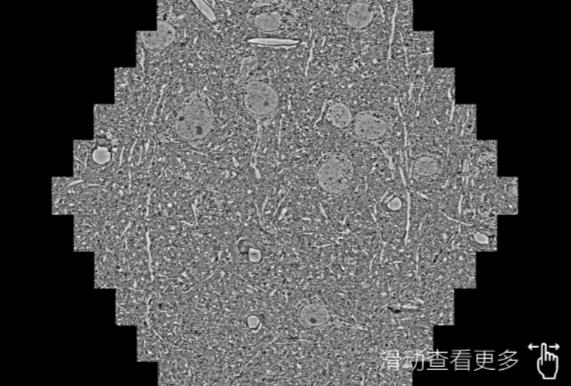

鼠脑切片。左图使用成都蔡司成都扫描电镜MultiSEM706对165μmx143pm面积区域成像,耗时仅需1.5秒。右图为鼠脑切片中30μm区域放大效果。样品由芝加哥大学B.Kasthuri提供。

使用蔡司高速成都扫描电镜MultiSEM对1mm²人脑皮层组织进行高分辨成像,并对其中的各种细胞结构进行三维重构分析。左图展示了2x3mm²组织平面中锥体神经元的三维重构效果。右图显示了局部体积神经元三维重构。图像由哈佛大学chtman实验室提供,渲染图由D. Berger 制作。